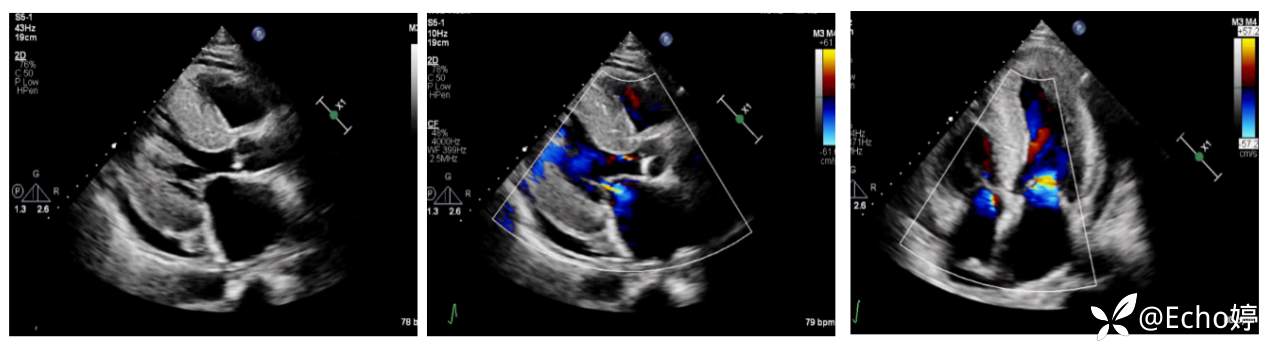

胸骨旁长轴、四腔心切面显示:左房增大前后径52mm,左室前后径偏小舒张末径35mm;

室间隔及左室壁弥漫性增厚,室间隔厚度26mm,左室后壁厚度25mm;

二尖瓣、主动脉瓣增厚;二尖瓣少中量返流,三尖瓣、主动脉瓣少量返流;少量心包积液。